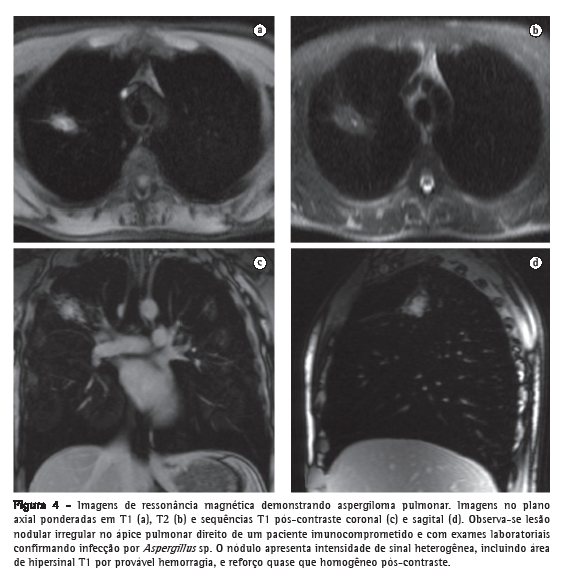

A RM é útil na caracterização das neoplasias pulmonares centrais com pneumonia obstrutiva ou atelectasia associada, diferenciando a massa tumoral das alterações secundárias, essas apresentando maior intensidade de sinal nas sequências ponderadas em T2, com aspecto mais homogêneo, devido ao acúmulo de secreções e de fluido, e com padrão de reforço diferente da lesão neoplásica.(34) Na aspergilose pulmonar invasiva, a RM é mais específica que a TC na caracterização das consolidações associadas a infartos hemorrágicos secundários à invasão vascular (Figura 4). As hemorragias aparecem como áreas de hipersinal T1, mais comumente periféricas, enquanto as imagens pós-contraste permitem identificar as áreas de inflamação ativa, necrose central e formação de abscessos. As características peculiares de sinal dos produtos de degradação da hemoglobina e de gordura também permitem que a RM auxilie no diagnóstico dos infartos pulmonares hemorrágicos, das hemorragias alveolares, como na síndrome de Goodpasture, e das pneumonias lipoides associadas à aspiração de óleo mineral.(35)